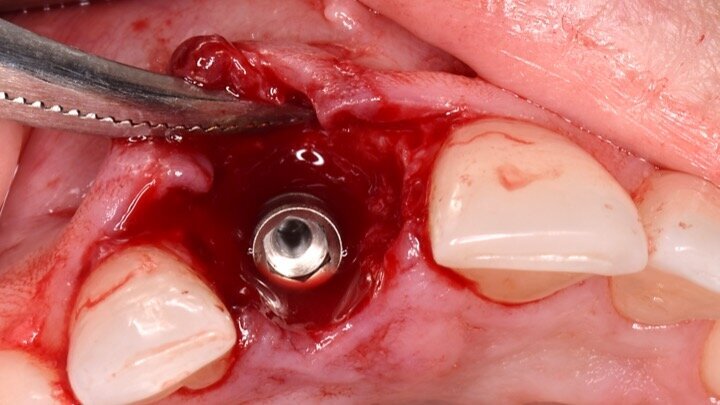

Figura 7. Implante de conexión interna insertado 2 mm por debajo de la cresta ósea, independientemente del defecto existente y a 55 Nw. Al no existir margen vestibular, tomamos como referencia los dos picos óseos de las papilas y entre ellos trazamos una línea imaginaria que los una enterrando el hombro unos 2 ó 3 mm por debajo de ella.

Figura 8. Esperamos a que la superficie del implante esté siempre cubierta por un coágulo de sangre antes de adaptar el material encima de éste.